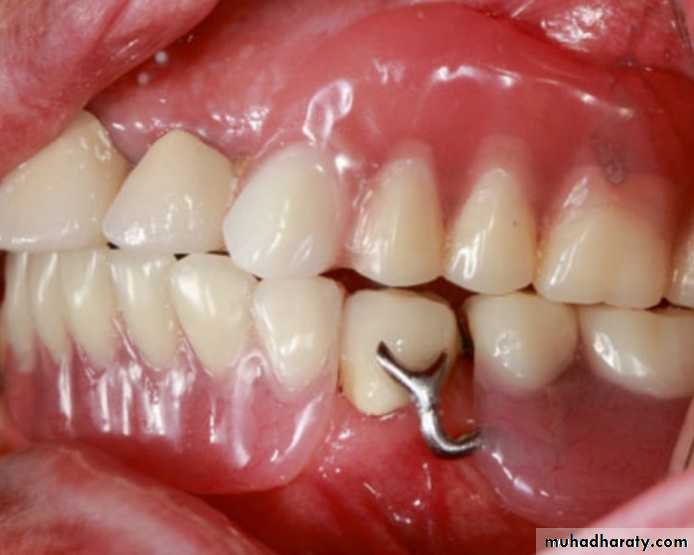

Tongue, cheek, or lip biting is a common com-plaint among patients receiving prosthodontic treatment.

Patients bite their cheeks mostly because of the inadequate occluding posterior teeth overlap.

With the use of monoplane posterior artificial teeth, this problem is seen more often because the teeth are arranged with no horizontal overlap.The cheeks may be trapped between the

occluding surfaces of the posterior artificial teeth, and painful ulcerations may be seen in patients wearing RPDs with inadequate posterior teeth overlap

The cheeks are trapped between the occluding surfaces of the posterior artificial teeth and painful ulcerations may be seen .